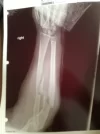

Brother Pls understand I mean you no disrespect with this question but I have to ask. You’re running Trenbolone in your cycle and benching 225-235 lbs? Are you getting over an injury? I wasn’t sure if I was missing something.

Yeah I’ve had some setbacks. Determined to get legit strong again before I’m too old, and get lean too. It’ll be a short PED career and I’m not a bodybuilder, but I’m not afraid to leverage the drugs to reach my goals.

View attachment 367455

That’s a hell of a break. Like I said brother meant no disrespect at all was just inquiring. Just be careful with stuff like Tren and Anadrol. They’ll get you stronger faster than your connective tissue can handle.